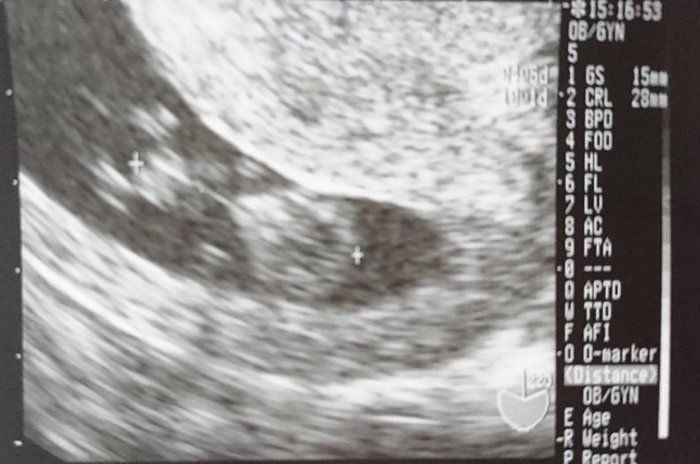

つぼいみきさんの妊娠9週目のエコー写真 手足が確認できる

初めてパパも一緒に病院へ行きました。画面にうつる我が子を見たパパは感動していました。手足が見えて、心臓も元気にパクパクと動いているのが確認でき一安心です。義母にもこの日のエコー写真を持って妊娠の報告に行きました。この頃、悪阻の一つなのか“ゲップ”がよく出るようになっていましたが、気持ち悪くて吐いてしまうようなことは一切なく、元気いっぱいのマタニティライフを楽しんでいました。